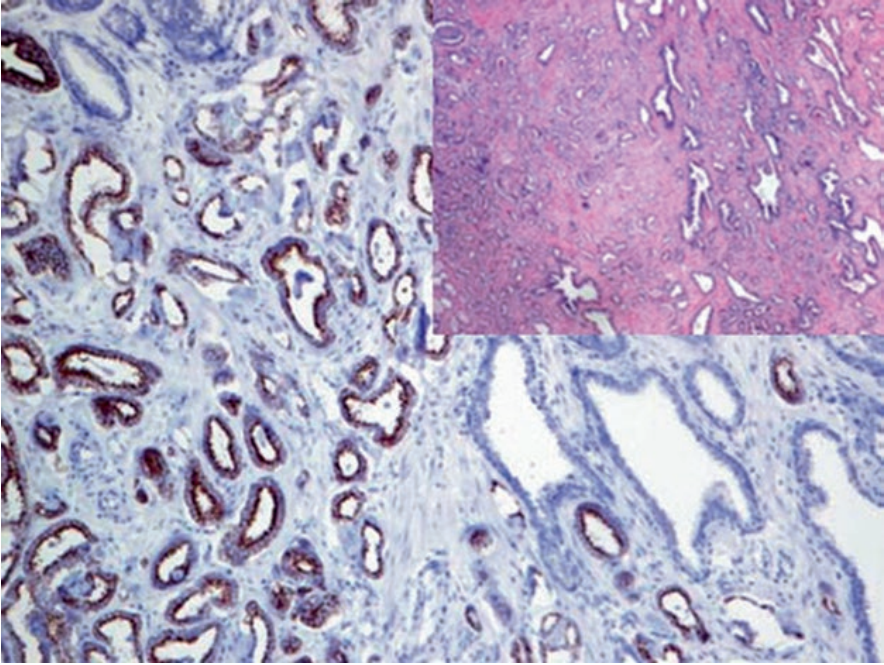

图2. 前列腺腺癌,高分子量CK(CK5/14)免疫组化,肿瘤性腺体并无基底层细胞。

NKX3.1在正常前列腺上皮及前列腺腺泡癌的细胞核中为强阳性表达。该指标对于原发前列腺癌相对特异,且细胞核着色的强度与肿瘤分化级别有关,低分化癌中表达极弱。

图3. 转移性前列腺癌,免疫组化NKX3.1在细胞核呈强阳性表达。

需要注意的是,NKX3.1也表达于睾丸原位生殖细胞肿瘤及原位精原细胞瘤,而浸润性精原细胞瘤和胚胎性癌中表达缺失。ER及AR阳性乳腺癌(如浸润性小叶癌)中,也有NKX3.1的不同程度阳性。涎腺的黏液单位及支气管腺体也可有NKX3.1的细胞核着色,在小活检标本中有利于结果判定。此外,肿瘤性淋巴细胞中可因为TAL-1基因异常而激活NKX3.1的表达。阳性表达模式:细胞核